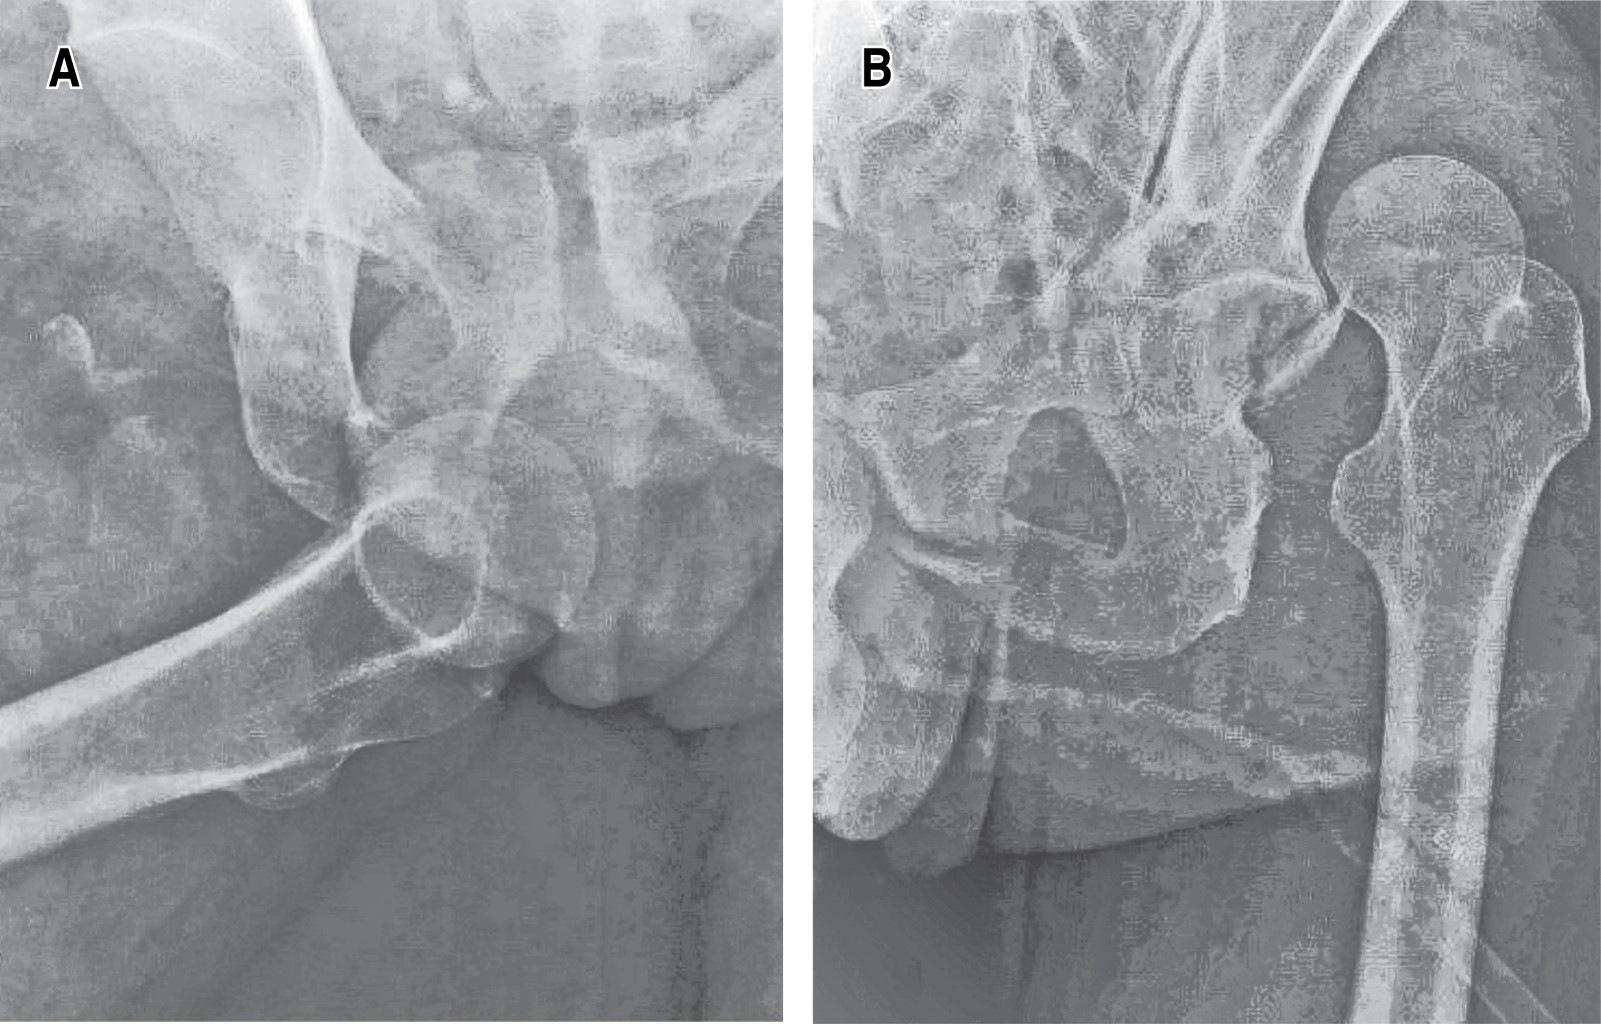

Inmediatamente se indicó cubrimiento antibiótico dual con cefalosporina de tercera generación y aminoglucósido, analgesia multimodal, profilaxis antitetánica; se realiza cubrimiento de la herida posterior a irrigación con solución salina fisiológica con apósitos estériles. Es trasladado a rayos X, donde se obtiene radiografía anteroposterior (AP) de pelvis, la cual evidencia luxación traumática anterior de cadera derecha (Figura 2) y luxación traumática anterior de cadera contralateral con fractura de ceja posterior del acetábulo, así como fractura de ambas ramas isquiopúbicas. Se obtuvieron laboratorios de ingreso, con una biometría hemática normal, función renal normal, glucosa en rangos normales, tiempos de coagulación sin alteraciones.

Después pasó a quirófano donde se realizó reducción abierta, ampliando la incisión; se disecó paquete neurovascular, el cual se encontró íntegro. Dada la dificultad para la reducción por tejidos blandos interpuestos, se optó por realizar miotomía de aductor mayor, así como de psoas, lo cual permitió la adecuada reducción. Posteriormente, durante la misma intervención, se realizó la reducción cerrada de la cadera contralateral. El resultado final de esta intervención se puede observar en la Figura 3, en el primer control radiográfico postquirúrgica.

Figura 2

Figura 3